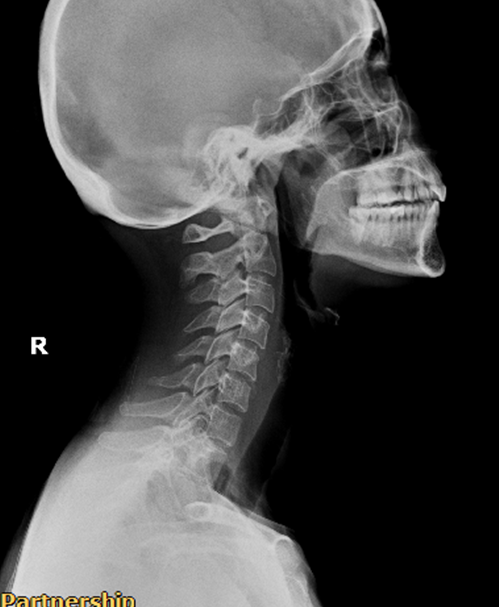

พนักงานออฟฟิศ (Case 3)

อาการ: ออฟฟิศซินโดรม / กระดูกคอตรง

"จากการนั่งทำงานหน้าคอมพิวเตอร์เป็นเวลานาน ทำให้กระดูกคอเสียความโค้ง หลังรับการฟื้นฟู สรีระคอดีขึ้น อาการปวดบ่าร้าวขึ้นศีรษะลดลงอย่างเห็นได้ชัด"

★★★★★